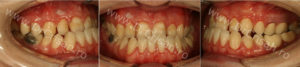

Pacientul în vârstă de 23 de ani retrognatism maxilar sever, anomalie scheletala cls III Angle. Cazul era depășit pentru a fi tratat exclusiv prin mijloace de corectare ortodontice…

Analiza cefalometrica, parte din diagnosticul ortodontic efectuat, sugera un retrognatism maxilar sever. Pacientul avea nevoie de tratament ortodontic combinat cu cel chirurgical.